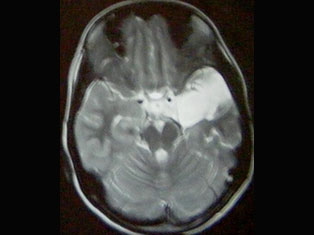

Brain Tumors

A brain tumor is a mass or growth of abnormal cells in your brain. Many different types of brain tumors exist. Some brain tumors are noncancerous (benign), and some brain tumors are cancerous (malignant).